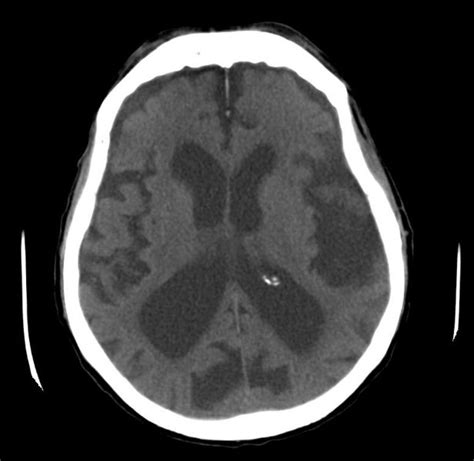

If you or a loved one is diagnosed with posterior cortical atrophy, the effects can be frustrating. In brain tissue, atrophy describes a loss of neurons and the connections between them. Brain atrophy refers to a loss of brain cells or a loss in the number of connections between brain cells. Brain atrophy, or cerebral atrophy, is a condition in which the brain or regions of the brain literally shrink in size. Posterior cortical atrophy, also called benson's syndrome, is a neurodegenerative disorder of the brain that produces a number of visual symptoms. In summary, atrophy is a macroscopic measure of nerve cells wasting away and dying. Cerebral atrophy or brain atrophy refers to the progressive loss of brain cells, called neurons, leading to decreased brain size. It can also only appear in a certain part of the brain. Kelly asks sabina about brain atrophy and what it is. On ct or mri, it will show enlarged ventricles, widened sulci, and narrowed gyri. Atrophy is a degeneration of either all or one part of the body, and is often referred to as wasting. it can occur for many reasons, but the two main causes are disuse and disease. Just how much recovery is possible remains to be seen, but in one study shown here, function returned to normal. A mild degree of brain atrophy is not always a concern.